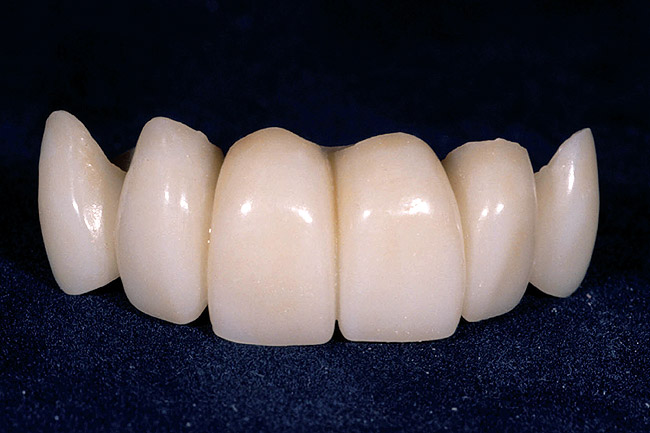

Figure 7  A full-arch temporary was placed to correctly identify an acceptable incisal edge position prior to surgery.

Figure 7